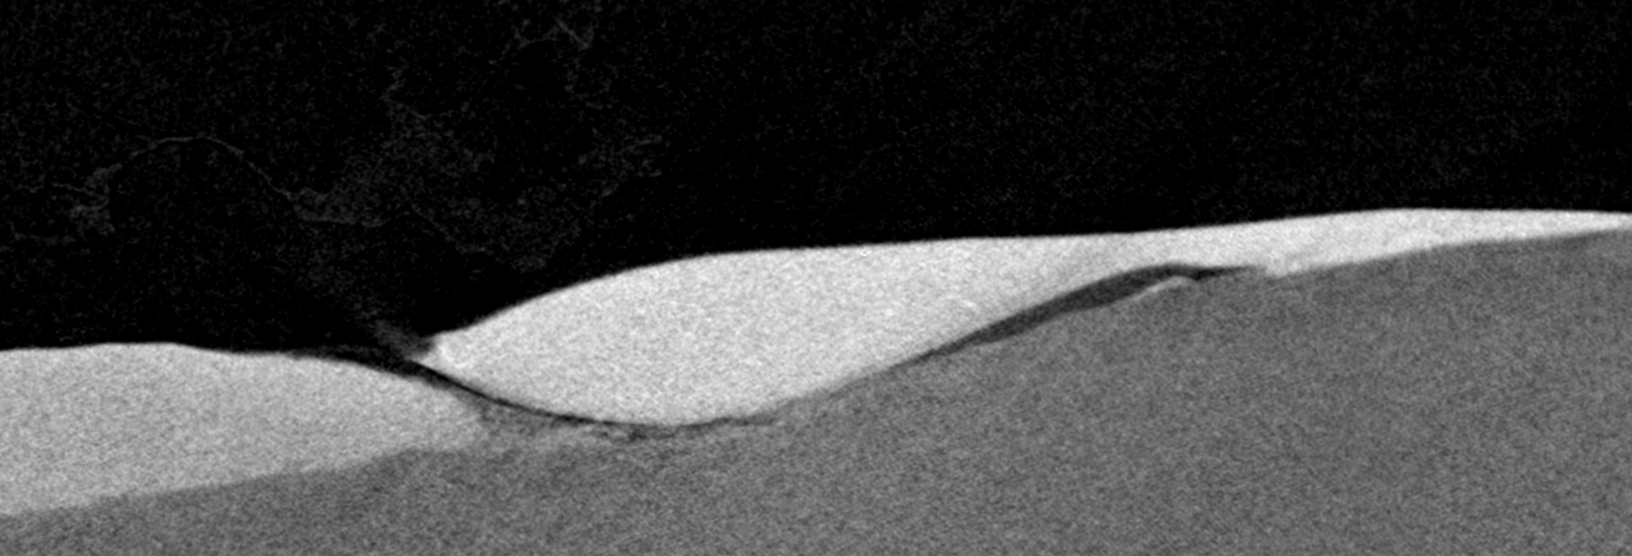

Ich würde gern ein OCT Bild und ein CT Bild aufeinander registrieren.

µCT Bild (im Anhang)

OCT Bild (im Anhang)